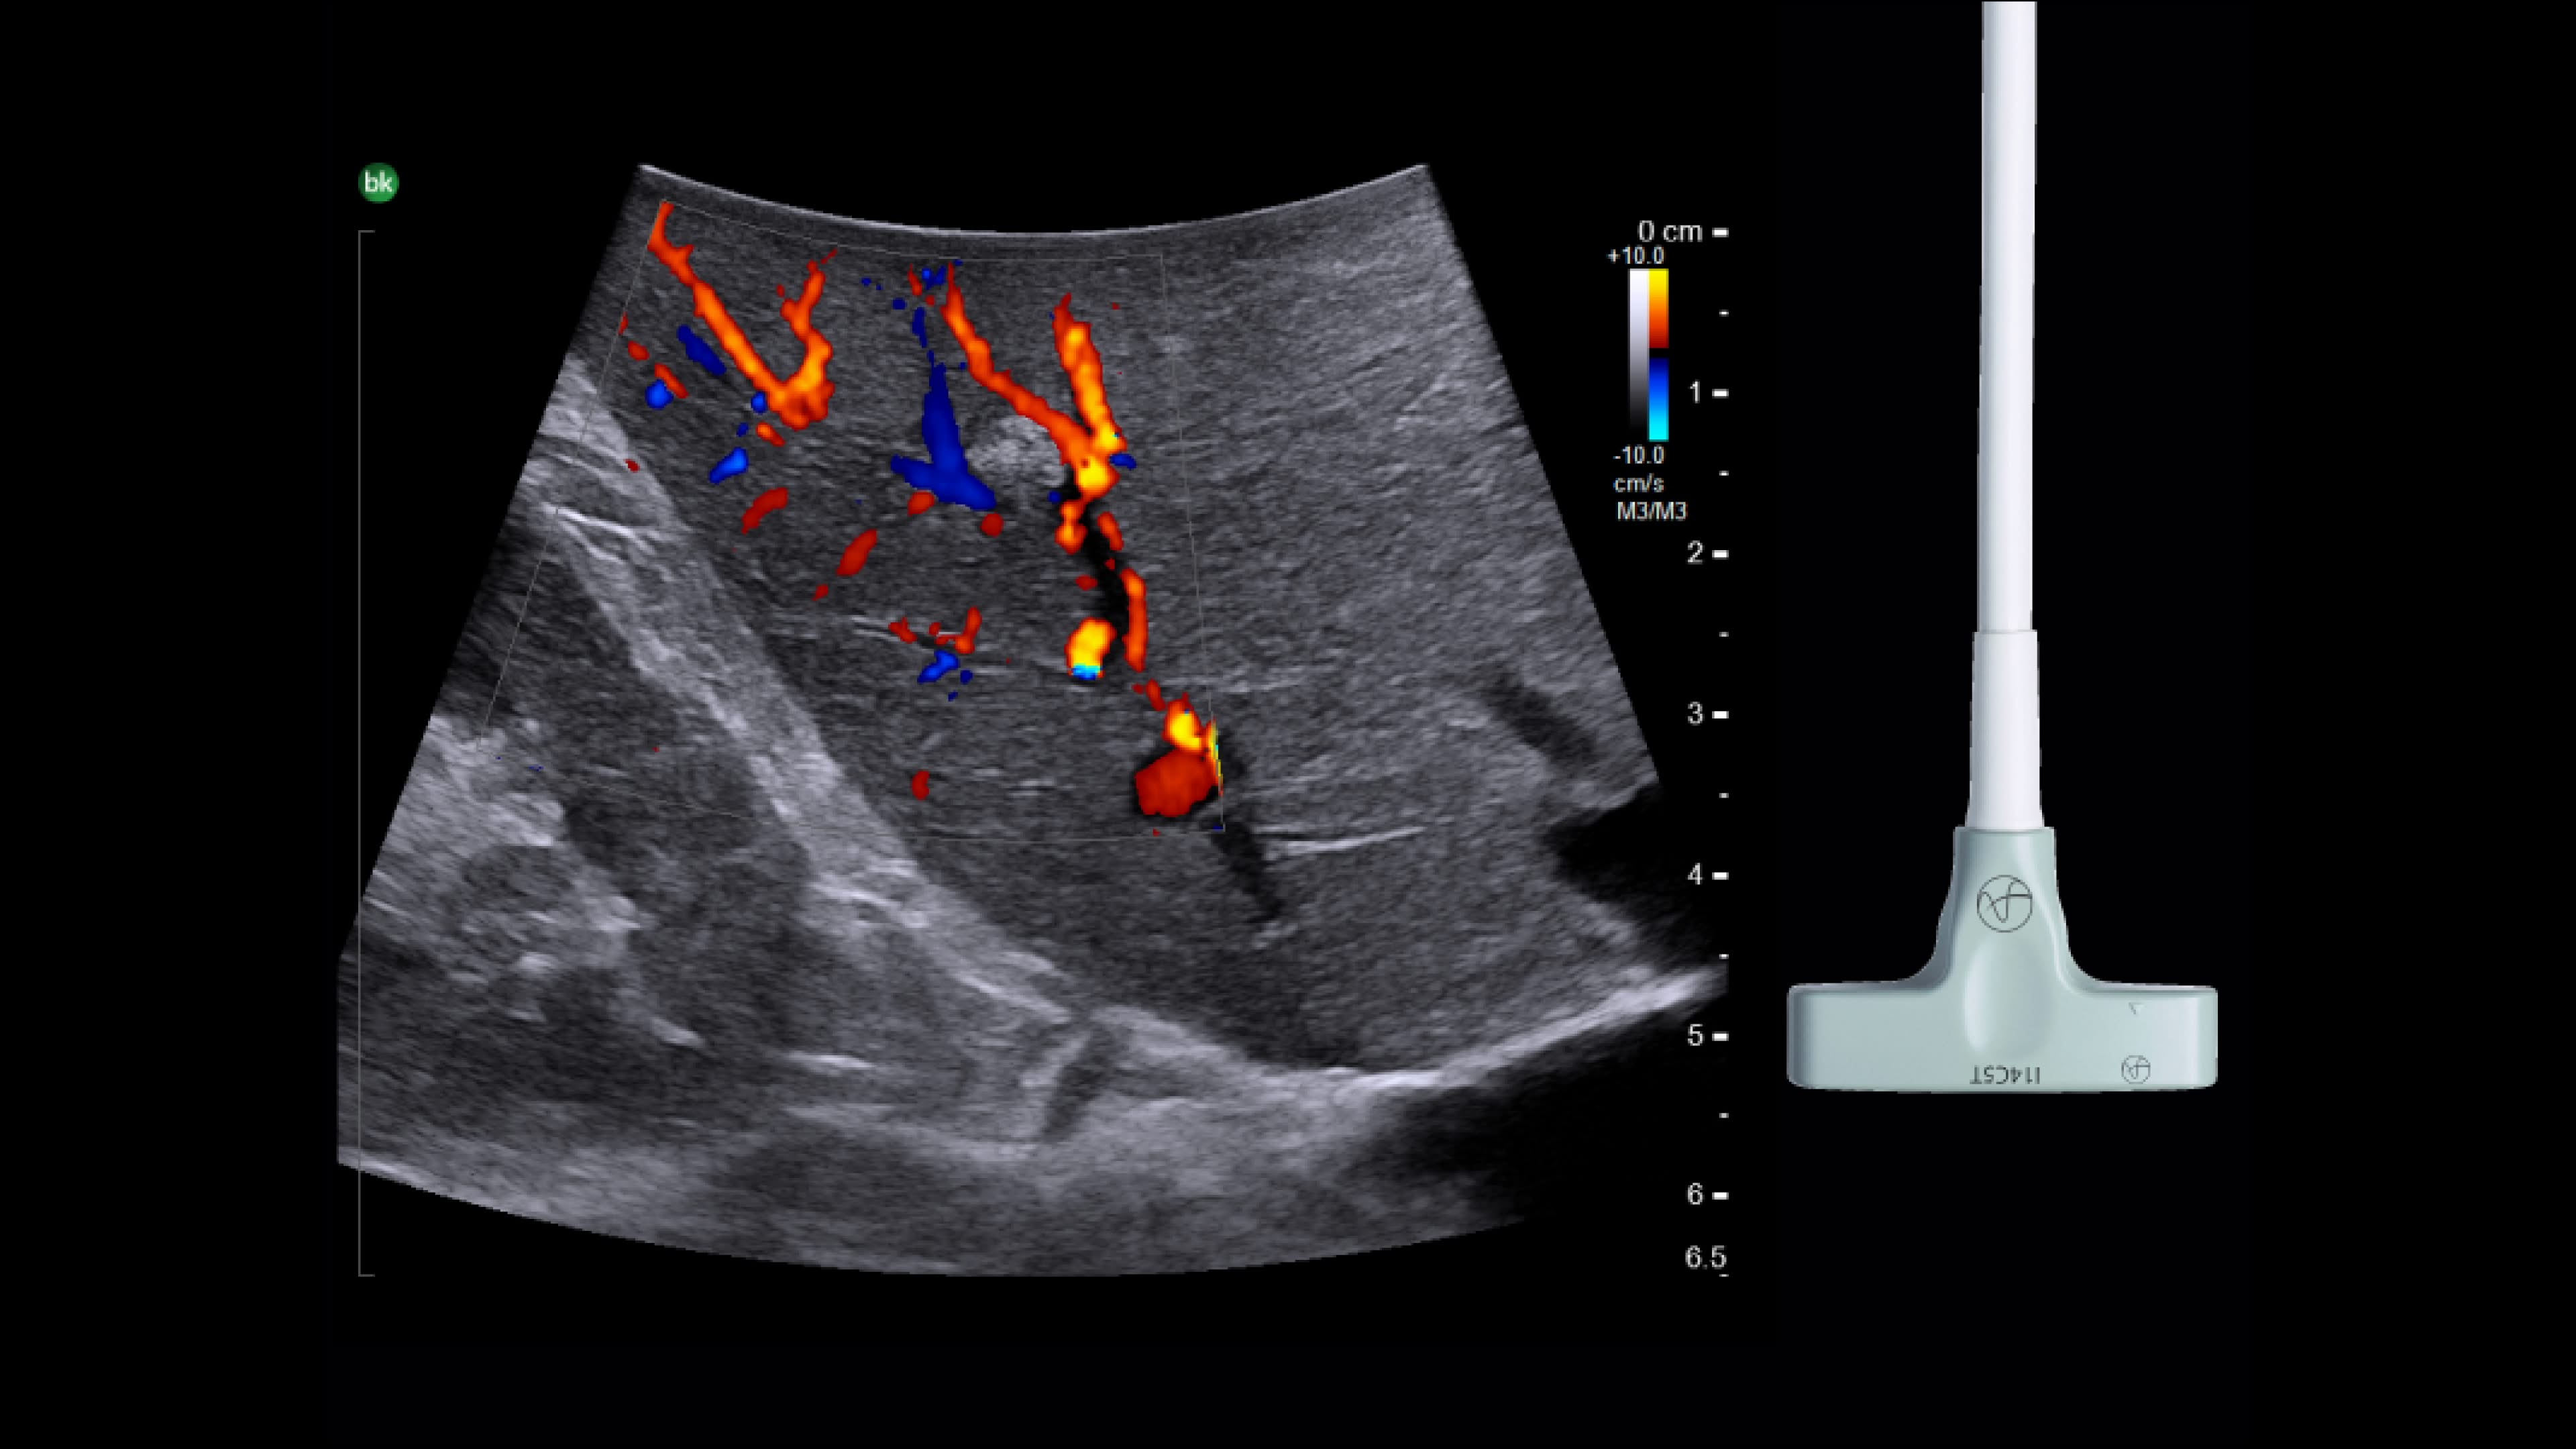

Robotics-assisted surgery

Robotics-assisted surgery with real-time intraoperative ultrasound allows surgeons to precisely locate and visualize anatomical abnormalities. Assess benign and malignant lesions, key arteries, veins, and other structures with high-resolution active imaging for enhanced surgical outcomes.